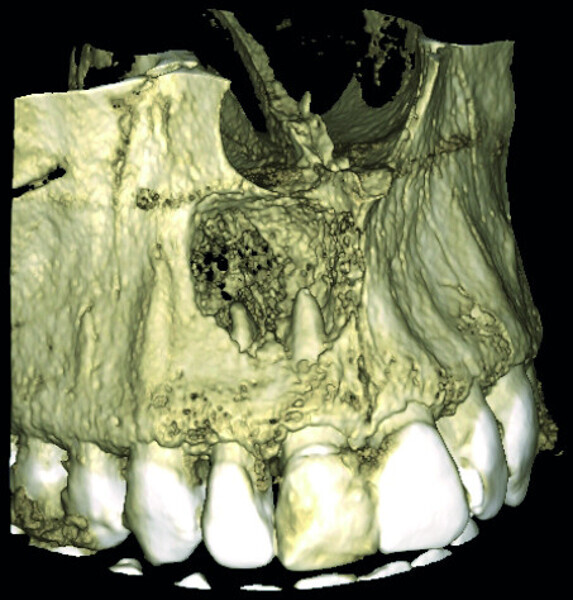

Fig. 1: Conventional radiograph of an endodontically treated tooth #11 and cold-sensitive tooth #12 compared with CBCT imaging showing the presence of a large apical bone defect (taken at a two-day interval).